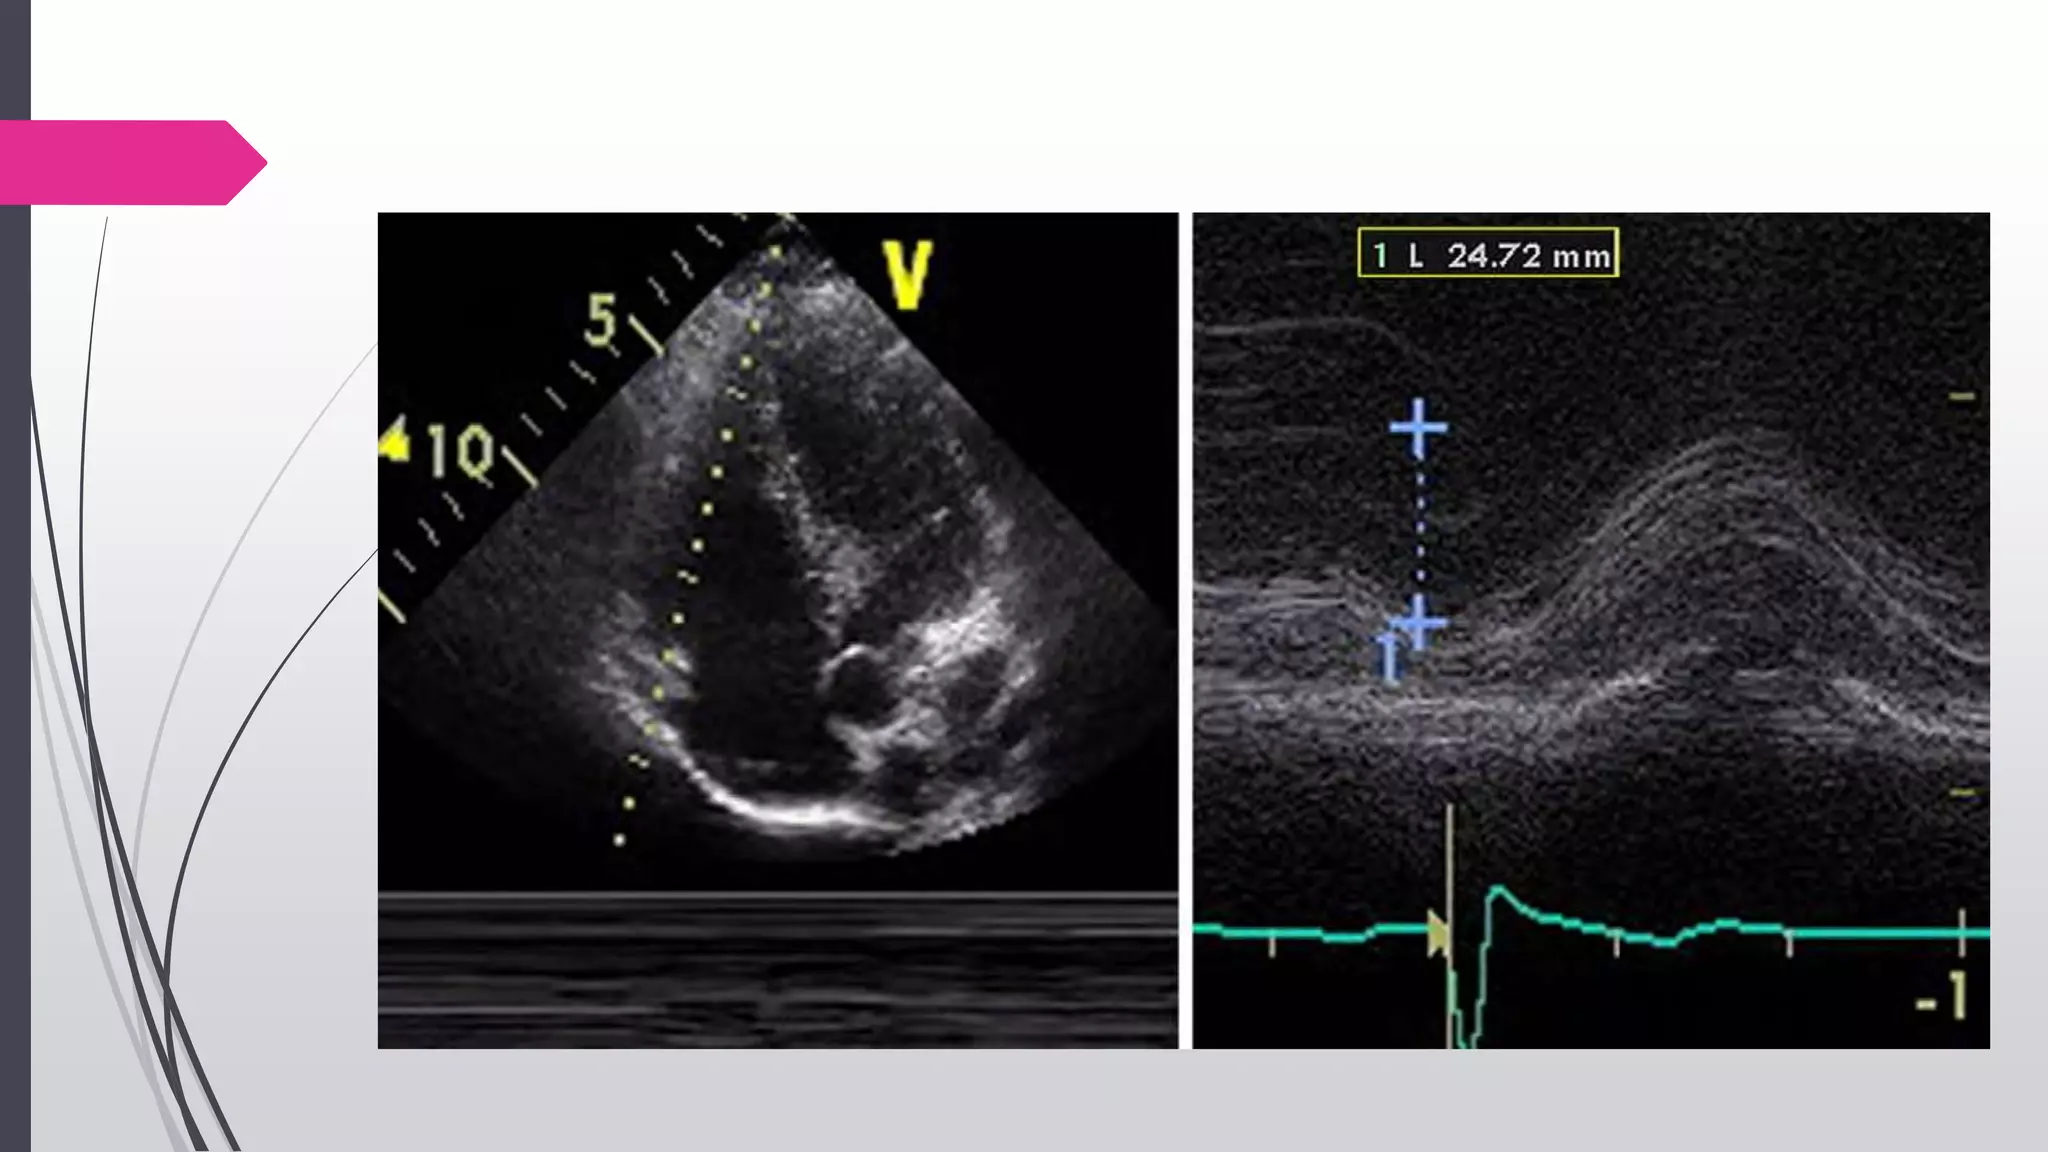

TAPSE or Tricuspid Annular Motion (TAM)

TAPSE or TAM is a method to measure the distance of

systolic excursion of the RV annular segment along its

longitudinal plane, from a standard apical 4-chamber

window.

Acquired by placing an M-mode cursor through the

tricuspid annulus & measuring the amount of longitudinal

motion of the annulus at peak systole

TAPSE <16mm → RV dysfunction